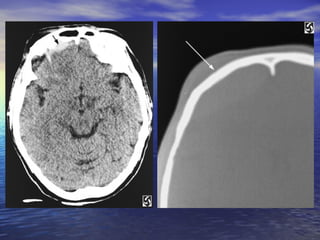

• #9 Slide #8 Epidural Hematoma Case A 32 y/o man presented to the ER after slipping on ice in his driveway. The patient fell backwards and hit his head on the ground. The patient got up and returned to his house and told his wife what had happened. After about 20 minutes of sitting the patient began complaining of a headache. Approximately one hour after the fall the patient became disoriented and obtunded. The patient's wife immediately called an ambulance, which brought him in to the ER. On arrival the patient was obtunded to the point that he could not answer or respond to questions. The CT on the left was taken shortly after arrival. Diagnosis: Epidural Hematoma On CT, epidural hematomas appear as well-defined, high attenuation lenticular or biconvex extra-axial collections. Associated mass effect with sulcal effacement and midline shift is frequently present. Overlying linear skull fractures can often be visualized on bone windows. If an epidural hematoma appears heterogeneous, containing irregular areas of lower attenuation, this can indicate active extravasation of fresh unclotted blood, requiring immediate surgical attention. Alternatively, areas of low attenuation can represent serum extruded from the clot.

• #10 Slide #9 CT of the head obtained without intravenous contrast enhancement shows a biconvex high-attenuation epidural hematoma adjacent to the right frontal lobe ( arrows ). The lesion extends superiorly to the level of the body of the lateral ventricle ( arrow )

• #11 Slide #10 and inferiorly to the roof of the right orbit (arrow). Mild mass effect is exerted on the subjacent brain parenchyma. A fracture is visible extending through the right side of frontal bone (arrow)

• #12 Slide #11 to the roof of the right orbit (arrow) with associated extracranial soft tissue swelling (arrow).